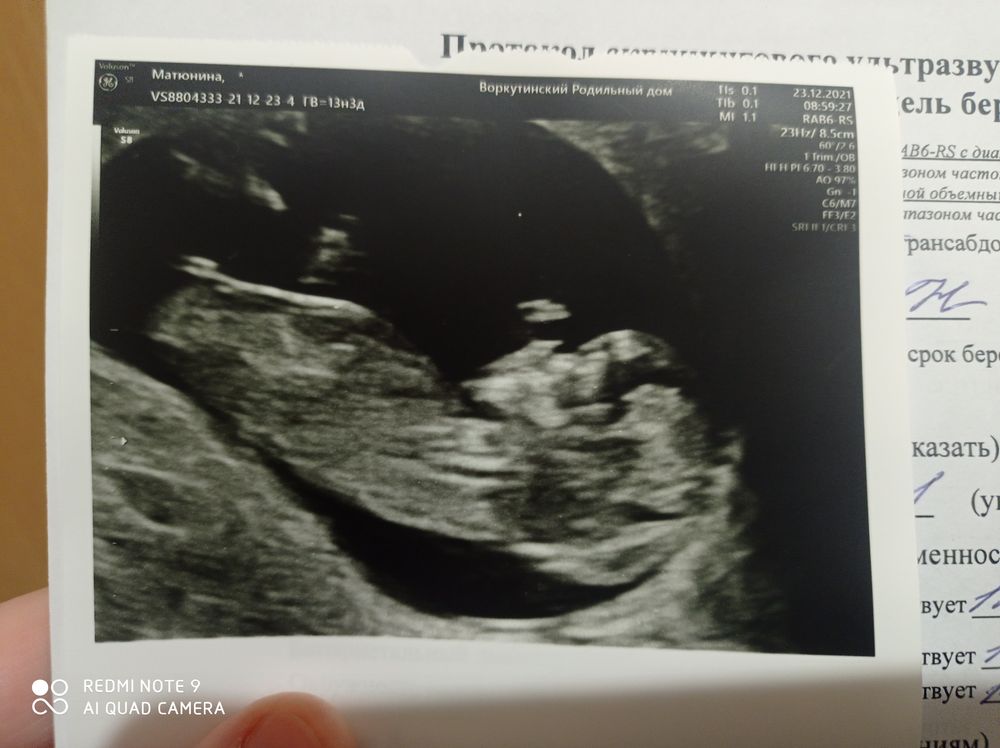

Алена Матюнина в Благополучная беременность 4 года Загадка✔ Сегодня был первый скрининг срок по УЗИ 13.3 Как думаете кого мы ждем? Доченьку или сына? Посмотрите еще 20 записей на эту тему Отменить Ответить Анна К Не понятно, не видно полового бугорка 23.12.2021 Ответить Святая инквизиция Ребёнка 😅 Тут не понятно, да и рано) не переживайте) 23.12.2021 Ответить Надежда Кажется, девочка 23.12.2021 Ответить Алена Матюнина Надежда, спасибо большое 😊 дай бог🤞🏼 23.12.2021 Ответить А Я почему то,за девочку 😅 23.12.2021 Ответить Алена Матюнина Анна, дай бог🤞🏼 23.12.2021 Ответить Лера У меня моя доця так ручкой всегда на УЗИ закрывалась ))) 23.12.2021 Ответить Бандаж. Все паникуют и я буду🙊 живот 🙇🏽♀️ Чаты Беременных Выберите чат: Январята-2026 Февралята-2026 Мартята-2026 Апрелята-2026 Майчата-2026 Июнята-2026 Июлята-2026 Августята-2026